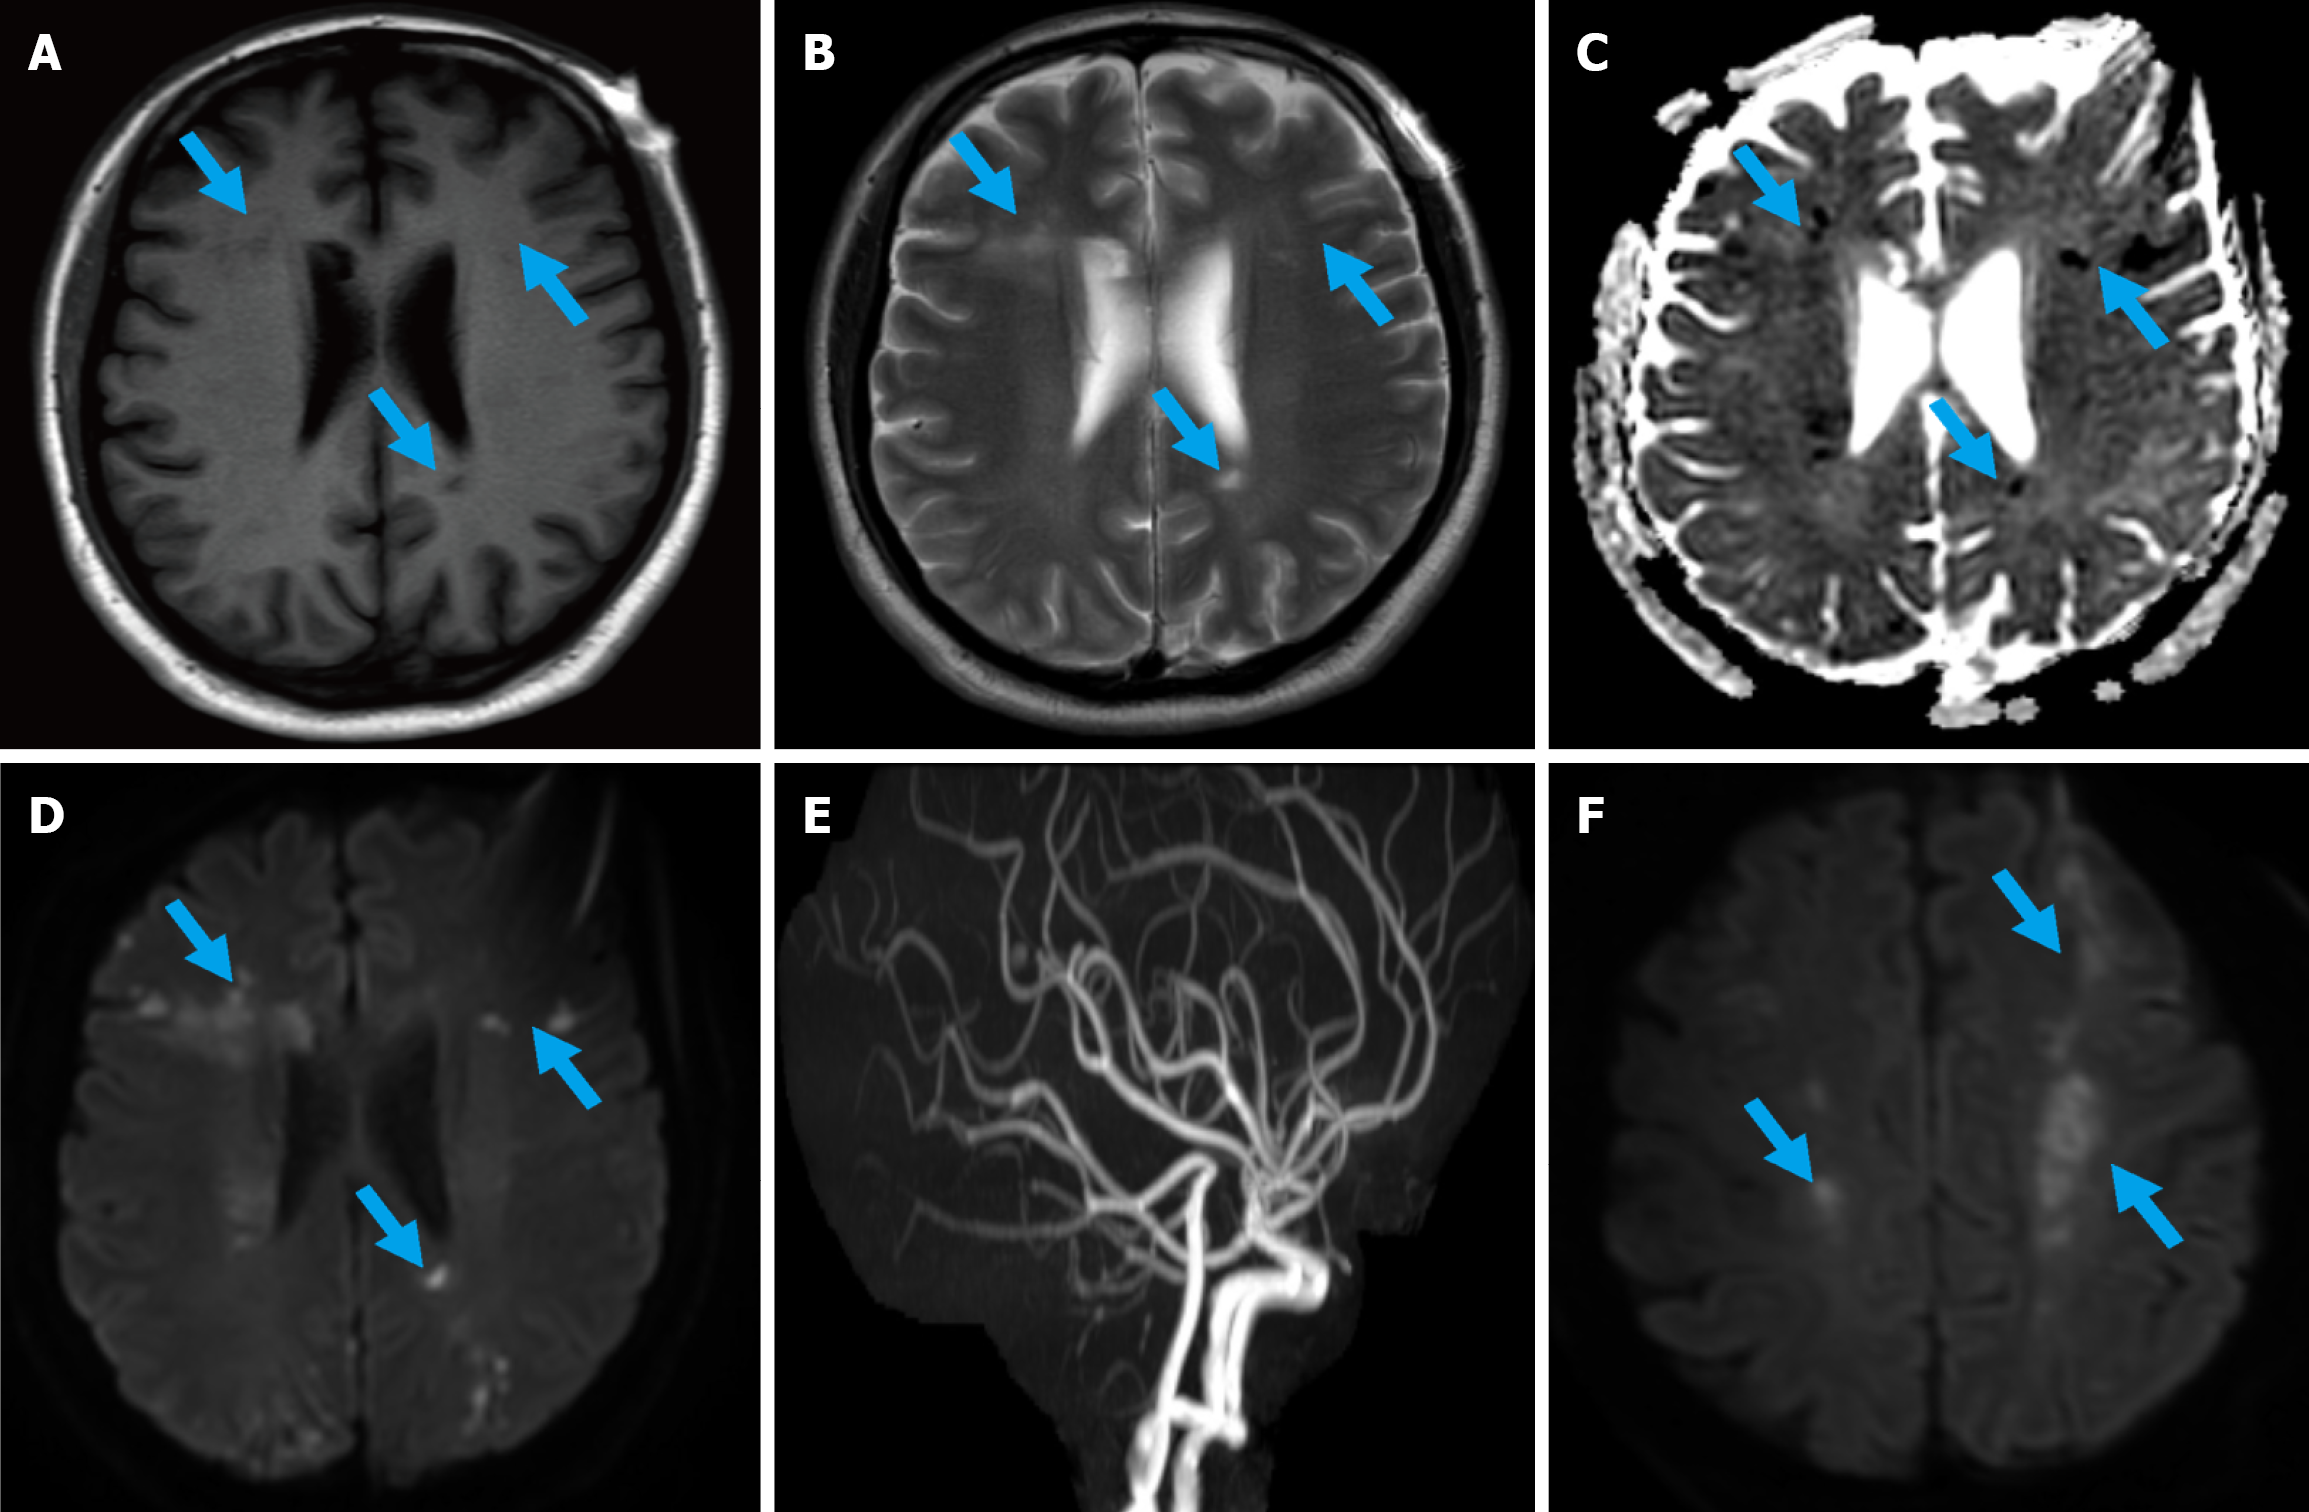

We aimed to perform an ultrasound-guided liver or pancreatic biopsy for pathological diagnosis. However, within just two days, the patient developed disorientation, characterized by impaired awareness of the surrounding environment. Magnetic resonance imaging plain scan showed scattered patchy long T1 and long T2 signals in the bilateral lateral ventricles, centrum semiovale and frontoparietal lobes, with high signal on diffusion weighted imaging (DWI) and low signal on apparent diffusion coefficient mapping (Figure 3A-D). Acute cerebral infarction was considered. However, cerebral magnetic resonance angiography showed no significant cerebrovascular stenosis, and the multiple intracranial infarcts could not be explained by the vascular distribution (Figure 3E). Thus, Trousseau syndrome was considered. Only one day later, the patient developed mixed aphasia, central facial paralysis, and right limb weakness. Repeat DWI revealed new infarcts in the bilateral parietal and frontal lobes (Figure 3F). The patient's performance status deteriorated rapidly during this period and only supportive treatment was allowed, with an extremely poor prognosis under pa